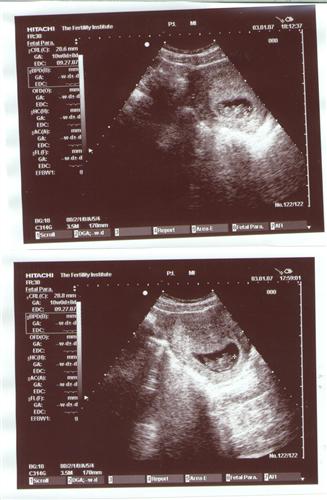

Re: 11 week sono pics..please share

This is my 10 week one...not a good pic but on the actual screen we saw arms and legs, and we even saw the little bugger moving around in there!! So amazing!!